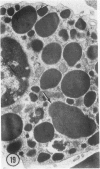

The prevalence of mast cells infiltrating bone marrow of different rats varied widely, as did the staining properties and size of their cytoplasmic granules. Bone marrow mast cells from several rats revealed large membrane-limited inclusions which stained metachromatically or orthochromatically and resembled inclusions in some macrophages. Ultrastructurally, mast cells varied widely in content of uniform dense granules or enlarged granules with less dense, fine grained content. Some of the large inclusions observed ultrastructurally in mast cells were heterophagic vacuoles which contained erythrocytes or reticulocytes, or remnants from other phagocytized cells, possibly neutrophils or unidentified homogeneous material. Smaller bodies, interpreted as fragments of erythrocytes, lay extracellularly near mast cells and occupied small, membrane-limited, heterophagic vacuoles in some mast cells. In other mast cells, communal vacuoles enclosed several specific cytoplasmic granules in various stages of disruption. The communal vacuoles occasionally opened to the extracellular space. A few large indeterminate vacuoles in mast cells contained amorphous flocculent matter which apparently derived either from coalescence of cytoplasmic granules through fusion of granule membranes or from endocytosis.